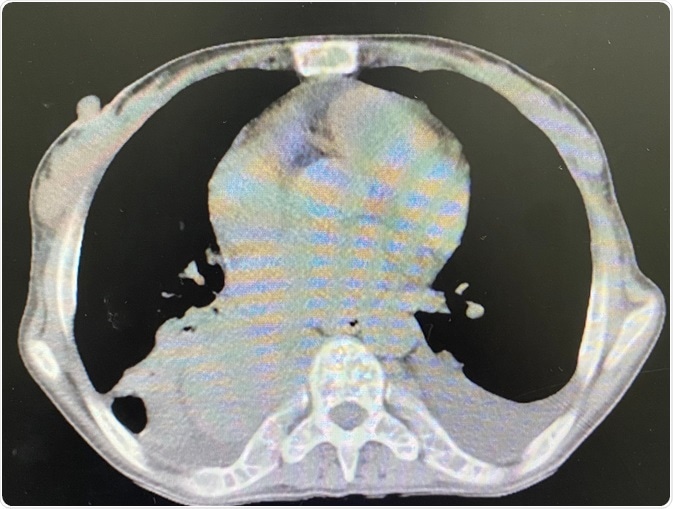

Mediastinal Mass

Image Credit: P.VARISA/Shutterstock.com